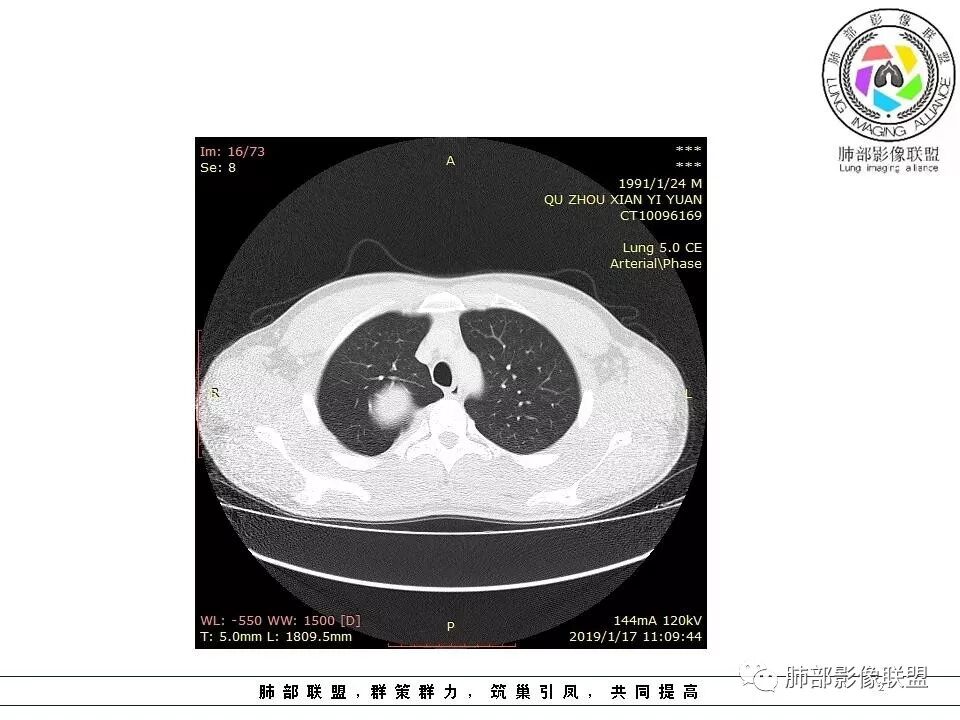

后纵隔脊柱旁占位性病变,疾病谱有神经鞘瘤,sft,节细胞瘤,髓外造血。此例有胸膜尾征,蛇纹征 ,延迟强化。考虑胸膜孤立性纤维瘤。看到有供血动脉,但不知道是哪里的血管。

后纵隔类圆形新生物,边缘光滑,胸膜尾征明显,贴近脊柱,蛇纹,血供丰富,考虑后纵隔软组织肿瘤,具体类型看不出来,鉴别神经鞘瘤。

后纵隔脊柱旁占位性病变,有胸膜尾征,胸膜下脂肪可见,蛇纹征,明显强化。考虑孤立性纤维瘤。

右侧后纵隔脊柱旁占位,边缘光滑清晰,内侧肺组织受压,外侧可见胸膜尾征,增强持续强化,并可见蛇纹血管征。考虑SFT

青年男性,右侧脊柱旁软组织肿块,边缘膨隆,密度不均,临近肺组织受压、胸膜增厚,增强后动脉期呈不均匀强化,并可见肋间动脉供血,延迟期强化较均匀,定位肺外,首先考虑SFT,神经源性肿瘤待排

青年男性,右侧后纵膈肿块,有胸膜尾征,支气管被推压,定位肺外,脏胸膜?血供来自肺动脉及肋间动脉,增强后有强化,蛇纹征,考虑SFT,鉴别鞘瘤

右肺占位,跨越上叶后段、下叶背,边缘光滑,瘤肺界面清,见肺压缩缘(线样不张`强化),见胸膜尾征,胸膜下脂肪未见明显增厚,肋骨丶脊柱未见侵袭及受压,渐进性丶地图样强化,冠状位似见体循环供血

诊断:SFT(来源壁层胸膜?一般小于20%)

右侧后纵膈肿块,有胸膜尾征,周围肺组织及支气管被推压,定位肺外,脏层胸膜来源,血供来自肺动脉或者支气管动脉,增强后持续渐进强化,蛇纹征,考虑SFT,鉴别鞘瘤。

青年男性,右后上纵隔脊柱旁沟可见团状软组织影,边界清,密度尚均匀,推挤邻近肺组织,胸膜可见掀起,有肺动脉供血,增强轻度蛇皮样强化,纵隔淋巴结未见肿大,邻近骨质未见破坏,胸膜下脂肪间隙消失,考虑SFT孤立性纤维瘤可能性大,鉴别神经鞘瘤,节细胞瘤,建议活检。

青年男性,胸痛,右上纵膈脊柱旁肿块,形态光整规则,支气管被推移,临近的胸膜明显增厚,有胸膜掀起,增强后密度不均匀,可见蛇形血管征,血供似乎有两根血管供血,考虑SFT

右后纵膈肿块,肺瘤界面清楚,胸膜尾征,邻近肺组织及支气管被推移,部分脂肪间隙存在,定位肺外来源,血供来自肋间动脉,增强后持续渐进强化,蛇纹征,考虑SFT,鞘瘤肿块内血管罕见,不考虑。

右上肺野脊柱旁软组织肿块,边缘光滑整齐,肺组织及气管右肺上叶支气管受压前移,外移,边缘可见胸膜尾征,病灶内密度不均,增强后渐进性持续强化,其内可见明显蛇纹血管征,首先考虑肺外来源,sft.可能性大

青年男性,右侧脊柱旁占位,瘤肺界限清晰,支气管推移,胸膜尾,D字征,胸膜下脂肪影,蛇纹血管,双重供血,延迟强化,定位胸膜,支持sft

边缘光滑,宽基底与胸壁相连,跨叶裂,叶裂稍前推,血管、支气管前移。

浅分叶

外上侧少量胸水

肋间动脉供血,强化尚均匀,逐步强化